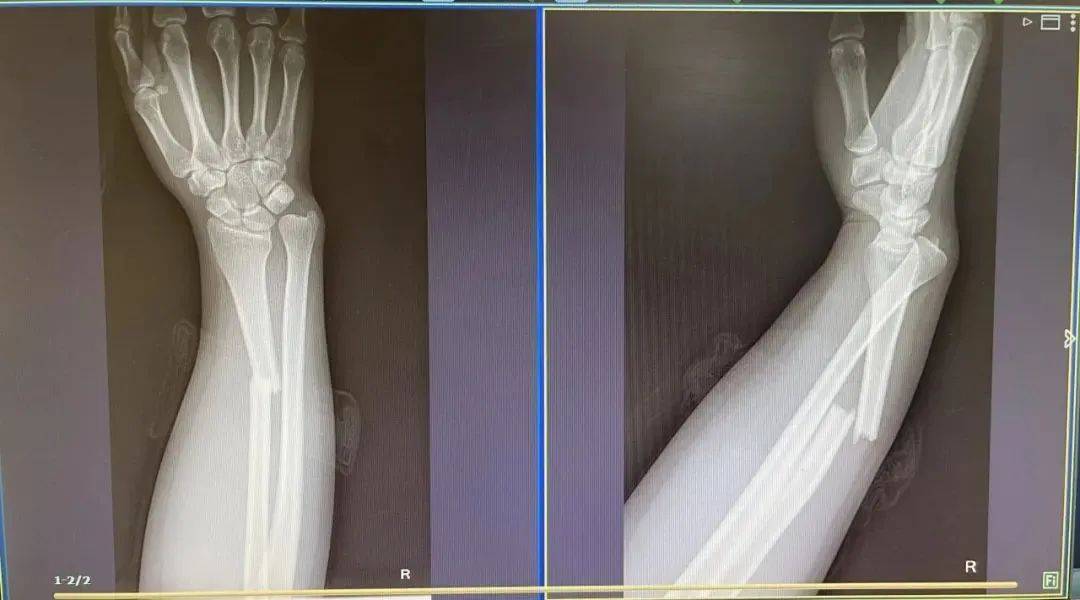

2023年,广西南宁,一幼童被父亲放在行李箱上推着走,不慎摔倒,下巴受伤出血。2019年,36岁的刘女士出游时,与孩子一同坐在行李箱上“滑行”,不料两人突然失去重心,摔倒在地,孩子脸部擦伤,刘女士手臂也骨折了。2019年,武汉一女童骑坐在行李箱上时,不慎连人带箱一起摔倒,导致下颌骨折,下巴磕伤,下唇和舌头被牙齿磕穿。医生提醒,普通行李箱既没有乘坐功能,也缺乏保护措施,再加上孩子坐在上面会动来动去,存在极大的安全隐患。而且孩子大多缺乏自我保护意识,由于惯性的作用容易摔倒,尤其以下巴磕伤最为常见,严重时甚至可能造成骨折。医生表示,如果孩子不小心摔伤,且受伤部位出现疼痛、肿胀或明显畸形,无法正常活动,家长应高度怀疑骨折的可能。此时切勿随意移动,可用硬纸板托住患肢并抬高,减轻肿胀,迅速就医。